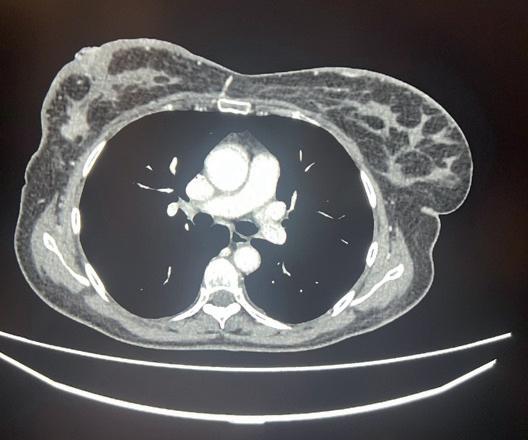

La TC total body con mdc effettuata per stadiazione oncologica, evidenzia fegato pressoché sostituito da lesioni ipodense tendenti alla confluenza di significato secondario, con multiple focali alterazioni della struttura ossea a carico del bacino, vertebre toraciche e lombari, sterno e coste.

La prima rivalutazione strumentale effettuata a Settembre 2023 con TC, dopo 4 cicli di trattamento, registra una risposta iniziale in sede epatica, una completa normalizzazione degli indici di funzionalità epatica così come dei marcatori tumorali e una stabilità strumentale della formazione mammaria e ascellare. Quindi, incoraggiati da un quadro clinico-laboratoristico drasticamente migliorato, si aggiunge paclitaxel 80 mg/m2 q7 al trattamento anti-HER2, sulla scorta dei dati dello studio di fase IIIB PERUSE.

Tuttavia, nonostante la buona risposta iniziale, la TC total body con mezzo di contrasto del 28/12/2023 (figura 1) evidenzia progressione epatica ed encefalica con un quadro radiologico che mostra sovvertimento encefalico diffuso caratterizzato da numerose lesioni secondarie (almeno 10) a netta impregnazione contrastografica a sede sia cerebrale che cerebellare, prevalentemente subcentimetriche, la maggiore di 13 mm in nucleo-capsulare sx con nucleo necrotico e modesto alone edemigeno perilesionale.